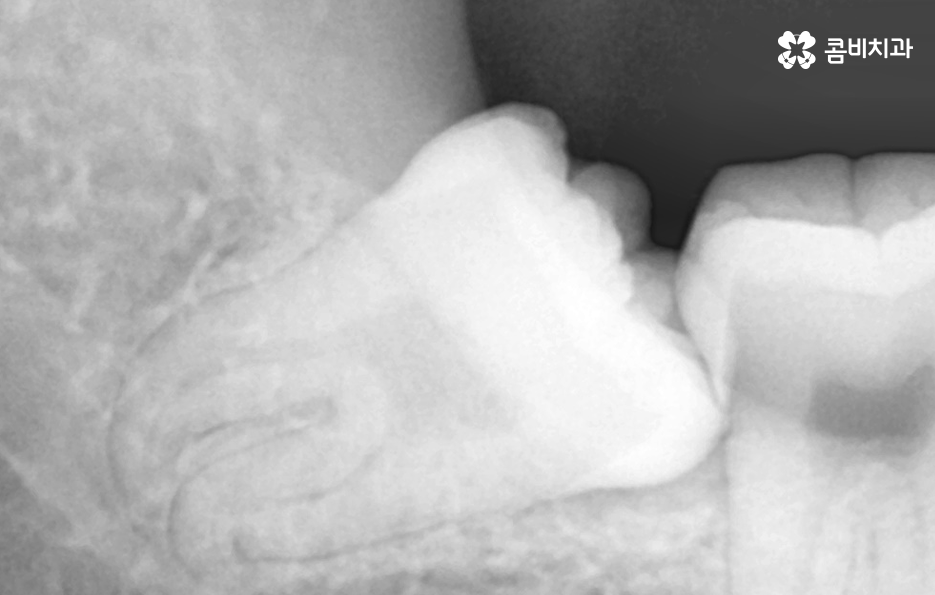

위 환자분의 사랑니 케이스를 살펴보면 윗니의 경우 정상 맹출된 사랑니의 형태를 보이지만 아랫니의 경우에는 부분 매복되어 있고 누워서 자라고 있는 사랑니의 형태를 볼 수 있어요. 다 그런 것은 아니지만 윗니의 경우 중력에 의해 정상 맹출된 사랑니의 형태가 좀더 많다면 아랫니의 경우 매복사랑니의 형태가 많은 편이기 때문에 하악 사랑니의 발치가 좀더 어려운 경우가 있어요

부분매복 사랑니는 이렇게 문제가 생겨요

부분적으로 맹출된 사랑니는 어금니와 사랑니 사이에 음식물이 끼기 쉽고 어금니 인접면에 사랑니로 인한 충치가 발생되기도 쉬우며 심한 경우에는 어금니의 뿌리 쪽 손상을 일으켜서 신경치료나 발치까지도 이르게 되는 경우가 있기 때문에 사랑니 발치 시점을 놓치게 되면 어금니 손상까지 커질 우려가 있어요